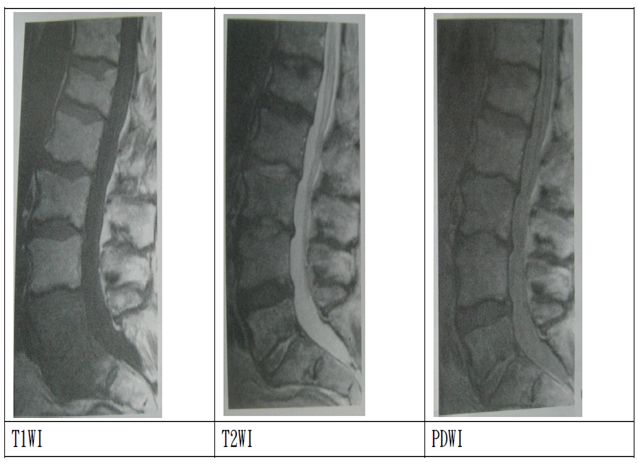

T1WI:

取短TR,使脂肪等短T1組織可充分弛緩,而腦脊髓液等長T1組織所呈現的弛緩量相對較少。

T2WI:取長TE,會將訊號中T1效應排除。長TE可凸顯出液體等橫向弛緩較慢的訊號。

PDWI:

稱作質子密度加權影像(proton density weighted image),主要是由組 織的質子密度差來產生影像對比度。使用長TR可使組織的縱向磁量充分 弛緩,以削減T1對訊號的影響,使用短TE是可以削減T2對影像的影響